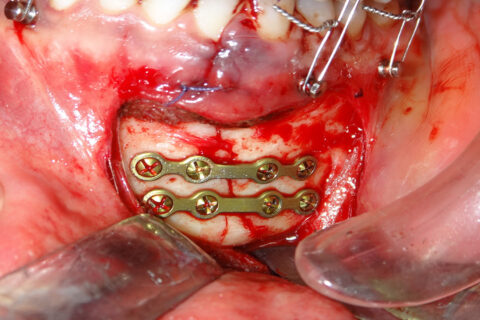

Facial / Jaw Bone Fracture Care

Expert surgical care for fractured facial and jaw bones.